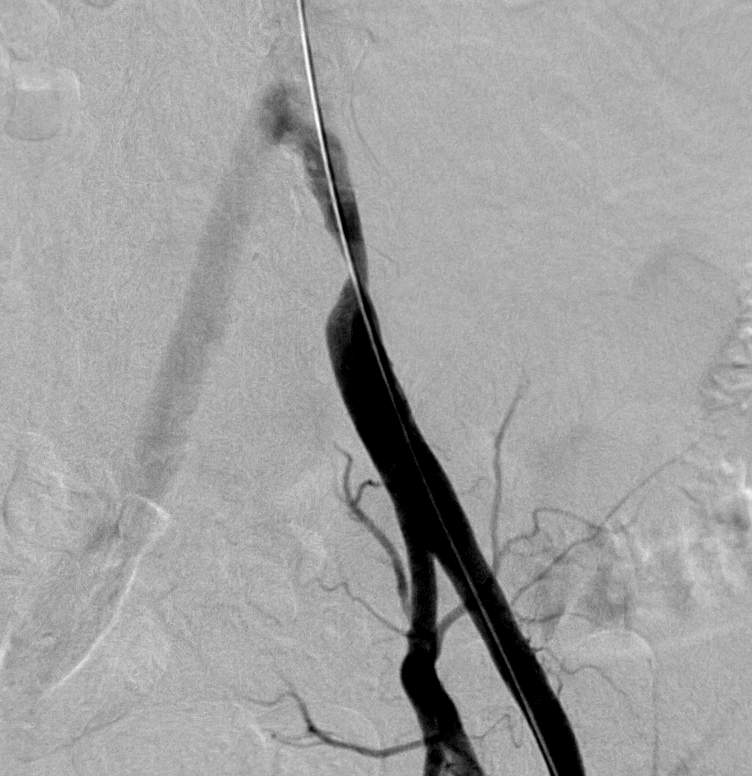

Placement of chronic venous lines and ports in Hungary are usually done by anethesiologists, whereas in many countries in Europe and in a few centers in Hungary it is performed by interventional radiologists; image-guidance (US-guided puncture, fluoroscopy guided placement of the catheter tip) reduces the risk of complications. Chronic venous access is necessary when chemotherapy, antibiotic therapy or total parenteral nutrition is needed for a number of weeks or months. The advantage of port is that it is placed into a subcutaneous pouch (as opposed to the Hickman line, which has a large portion of the catheters outside the skin) thus the quality of life of the patient is much better. The port is (almost) invisible, regular lifestyle including showers and swimming is possible, it can be used for many months or even 1-2 years, and it can be punctuted more than 1000 times; the catheter is tunneled from this pouch to the internal jugular vein or the subclavian vein; the tip of this catheter is in the distal portion of the superior vena cava (Figure 10). Most important immediate complications at these procedures include PTX, inadvertent arterial puncture, venous wall perforation, air-embolism, catheter malposition; delayed complications include infection, venous stenosis, formation of thrombus or fibrin sheath.

Figure 10. Port implantation. The port chamber is indicated by the solid arrow. The plastic catheter from the port chamber is directed through a subcutaneous tunnel into the internal jugular vein and the superior vena cava (dashed arrows). Internal jugular vein was punctured using ultrasound guidance.